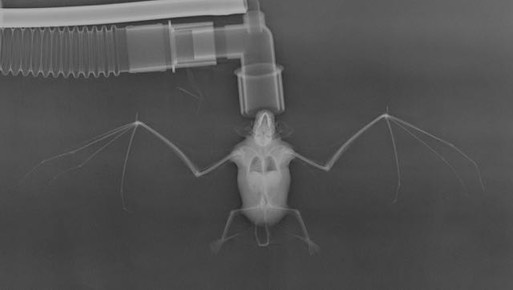

There were nine admissions this past week, eight raptors and one Silver-haired Bat. The bat weighed a plump 13 grams and appeared to be uninjured. He probably picked the wrong place to roost and was disturbed, ending up on the ground. We gave him some fluids and sent him on his way.